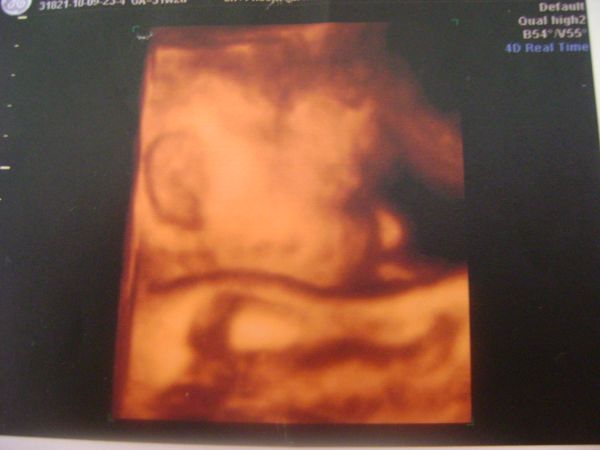

szóval, ha kisfiú, akkor Mátyás lesz, ha viszont tényleg kicsi lány, akkor Lilla, vagy Izabella, attól függ, hogy milyen lesz születésekor! ha olyan mexikói "szépség", akkor apa belemegy az Izába, ha viszont nem, akkor marad a Lilla!

és végezetül egy aktuális fotó, végre készült rólam egy valamelyest normális, már, ami a hasamat illeti! itt 31 hetes és 5 napos vagyok, még vacsi előtt!